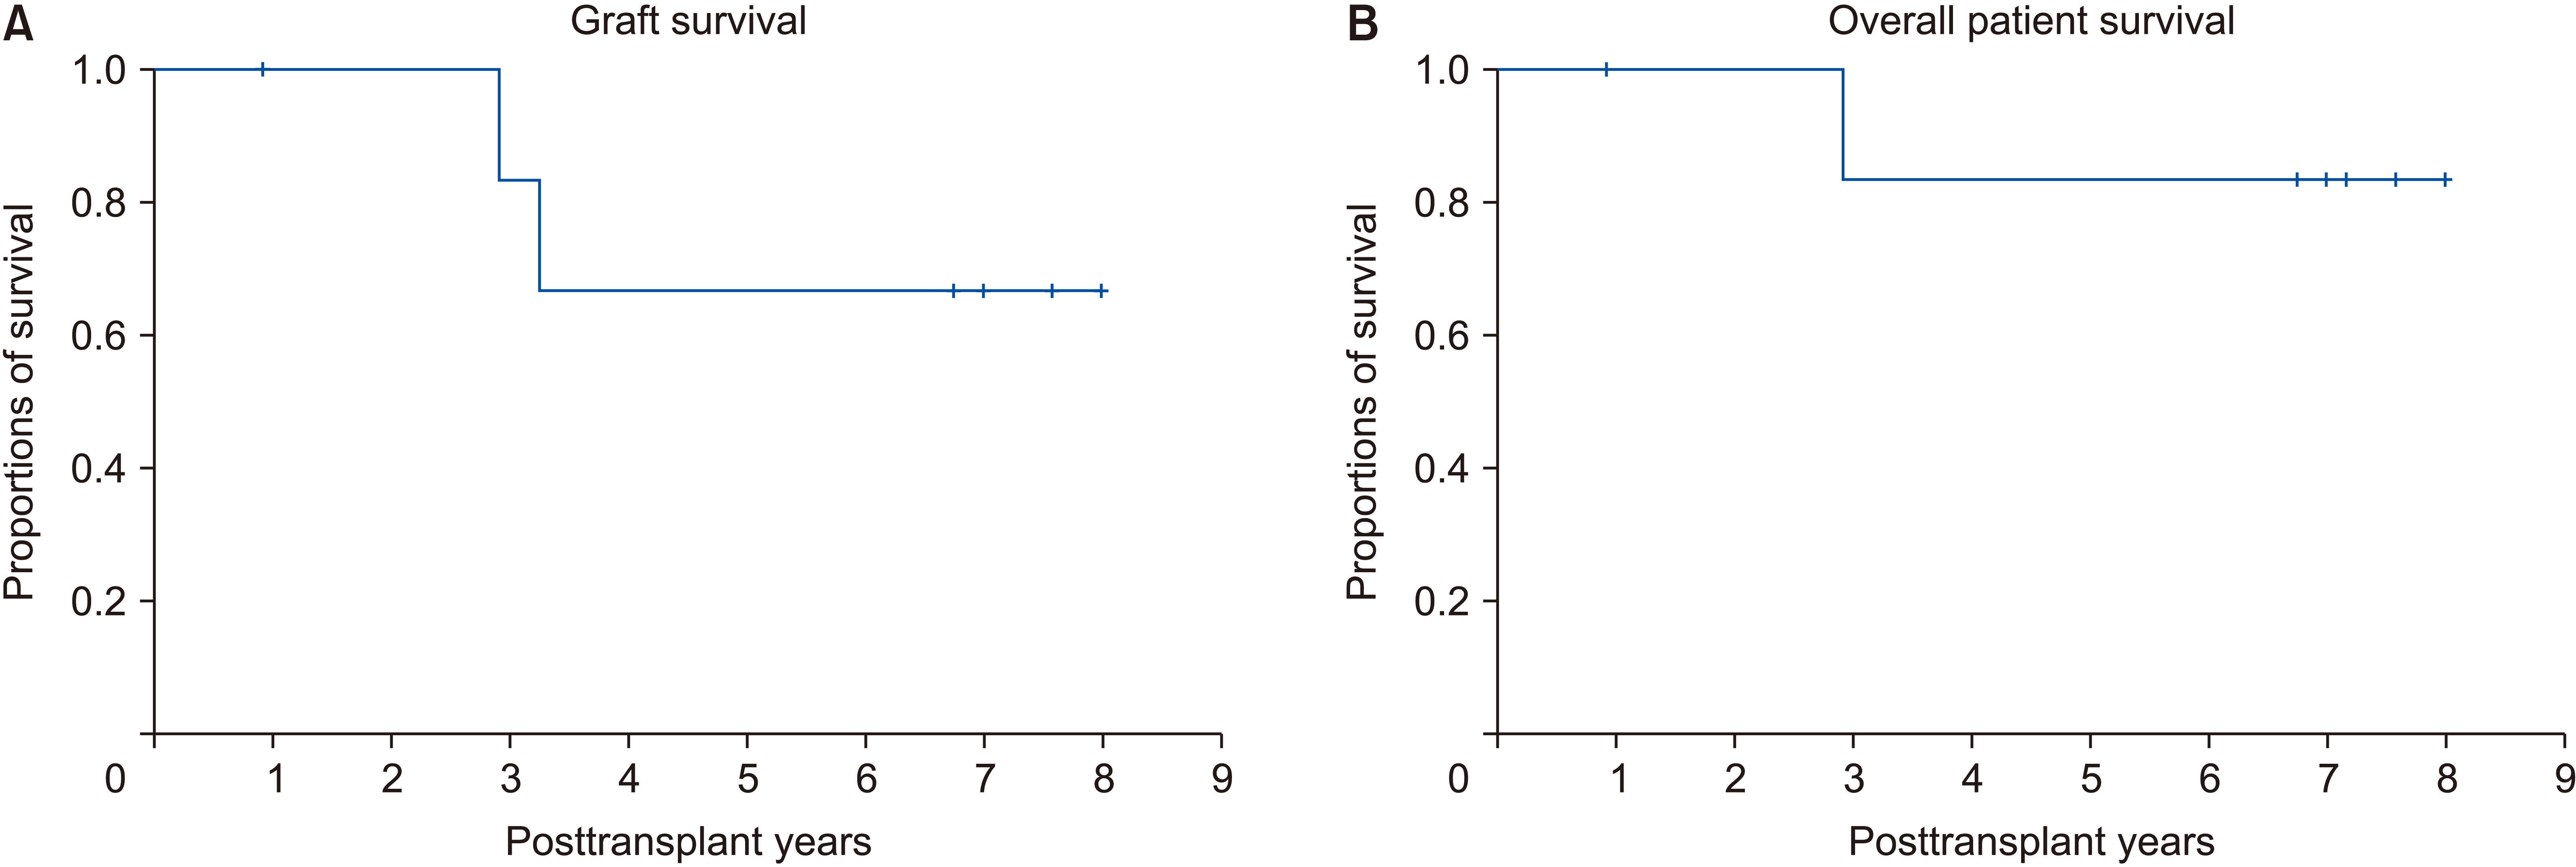

Two and five patients were diagnosed with PFIC type 1 and type 2, respectively. For all seven patients, age of PFIC onset was at birth. Jaundice was present in all cases. Mean pretransplant total and direct bilirubin levels were 16.1 ± 8.1 mg/dL and 12.4 ± 6.2 mg/dL, respectively. Median patient age and body weight at LT were 10 months and 7 kg, respectively. Types of donors were mothers of patients in four and deceased donors in three. All five patients with PFIC type 2 recovered uneventfully. One patient each with PFIC type 1 underwent retransplantation due to graft failure or died due to multi-organ failure. Overall graft and patient survival rates at five years were 66.7% and 83.3%, respectively. Bile salt export pump immunohistochemical staining showed normal canalicular expression in two patients with PFIC type 1, focal loss in two patients with PFIC type 2, and total loss in three patients with PFIC type 2.

Conclusions

LT is currently the only effective treatment for PFIC-associated end-stage liver diseases. It is mandatory to perform regular follow-up due to the risk of complications including steatohepatitis, especially for patients with PFIC type 1.